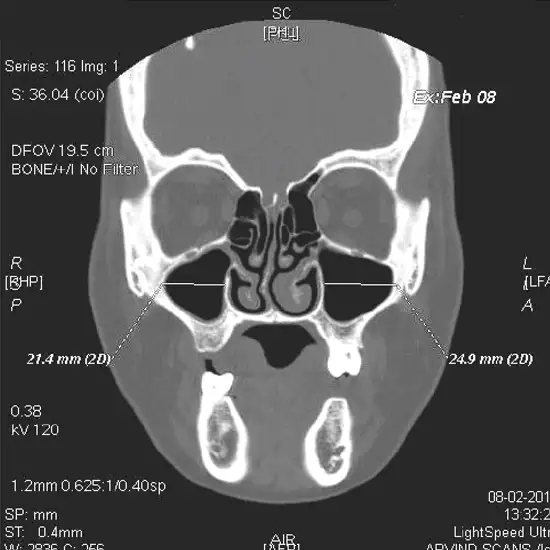

CT scan Maxilla Coronal is an imaging procedure used to create detailed images of the maxilla and its surrounding bones, tissues, skin, and muscles at the coronal. This scan is recommended to diagnose the infection, injury, and other abnormalities in the upper jaw.

Your doctor orders a CT scan of Maxilla Coronal to diagnose the upper jaw, its bones, and surrounding tissues and the problem associated with it. It is helpful in the effective detection of Infection, Inflammation of the maxillary sinus, trauma/ injury in the maxilla bone, abnormal growth, and tumours in the maxillary region.